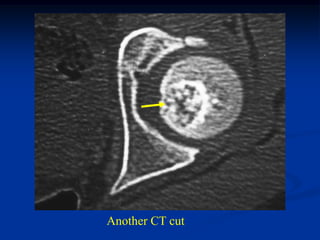

Case #120

38 year female

enchondroma

distal femur

Tumor seen thru cortical window